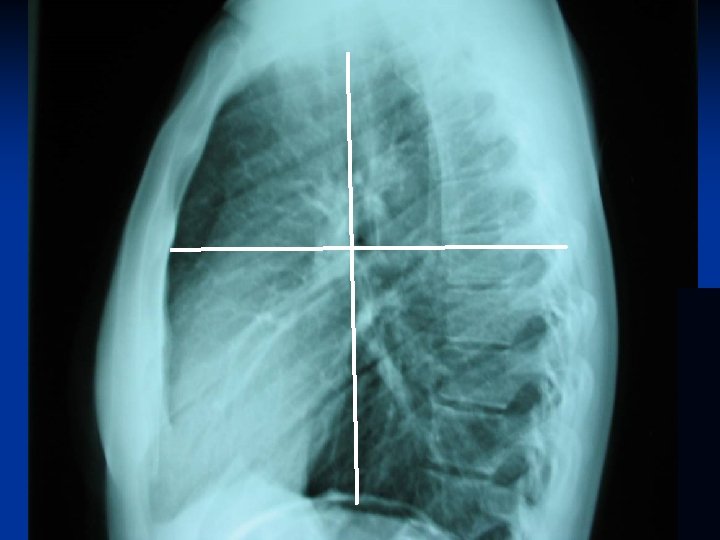

Radiograma em Perfil

Interpretação do Radiograma tórax - Perfil Sinal da coluna v coluna dorsal mais visível de cima para baixo v maior quantidade de músculos na parte superior do tórax v menor volume de ar pulmonar nesta região